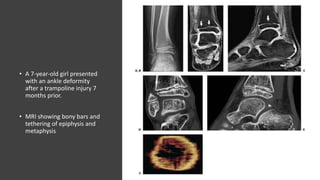

• A 7-year-old girl presented

with an ankle deformity

after a trampoline injury 7

months prior.

• MRI showing bony bars and

tethering of epiphysis and

metaphysis